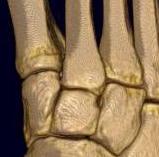

Anatomy

Bony Stability

| Alignment | Alignment | Roman arch | Keystone / Mortise |

|---|---|---|---|

|

1st metatarsal - medial cuneiform 2nd metatarsal - middle cuneiform 3rd metatarsal - lateral cuneiform

AP foot view |

4th and 5th metatarsals articulate with cuboid

Oblique foot view |

Bases of metatarsal wider dorsally than plantar Form half of Roman arch |

2nd metatarsal is keystone of transverse metatarsal arch - middle cuneiform is recessed proximally - mortise provided for base of second metatarsal |